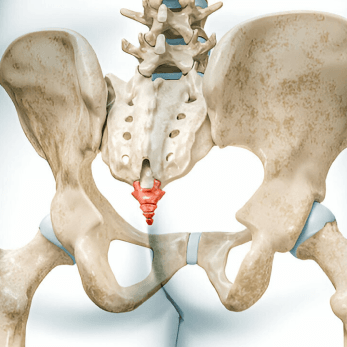

Anatomy of the Coccyx

Coccyx is the distal most part of the spine. It is triangular in shape and comprises of 3-5 fused segments. It serves as one leg of the tripod, also comprising of the two ischial tuberosities and this tripod forms the weight bearing surface in a seated position. It forms a central connecting point for various pelvic floor muscles which support the anus, vagina in females and also play a supporting role in defecation, walking and running. (Diagram to be added)